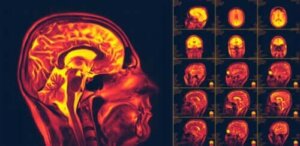

Neuroplasticiteit in de hersenen, ook wel hersenplasticiteit genoemd, is een van de belangrijkste recente ontdekkingen over het menselijk lichaam. Het is het vermogen van de hersenen om te veranderen en zich aan te passen aan nieuwe gedragingen of ervaringen.

Wetenschappers ontdekten echter dat onze hersenneuronen voortdurend kunnen regenereren. Dat doen ze niet alleen anatomisch, maar ze kunnen ook nieuwe verbindingen vormen. Dit concept is algemeen bekend als “neuroplasticiteit.”

Daarna begonnen ze verschillende beeldvormings- en stimulatietests uit te voeren om aan te tonen dat er neuroplasticiteit bestaat. Wetenschappers onderzoeken nog steeds alle aspecten van dit fenomeen.